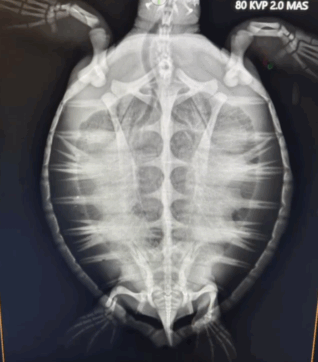

Name: BLT

Species: Green Sea Turtle

Weight: 6.4lbs.

Reason for visit: Fibropapilloma (FP) tumors, Lethargic

- 8/6/2025 – Meet BLT! a juvenile green sea turtle that was rescued off of Key Largo where he was found lethargic and with light fibropapilloma (FP) tumor load. we suspect BLT may have neurological challenges from biotoxin. Treatment for BLT includes IV nutrition, fluid, antibiotics and a healthy diet of greens and mixed sea food. Blt’s Blood plasma was collected and sent to a lab to test for biotoxins.

- 10/21/2025- BLT will be receiving a CT scan soon!